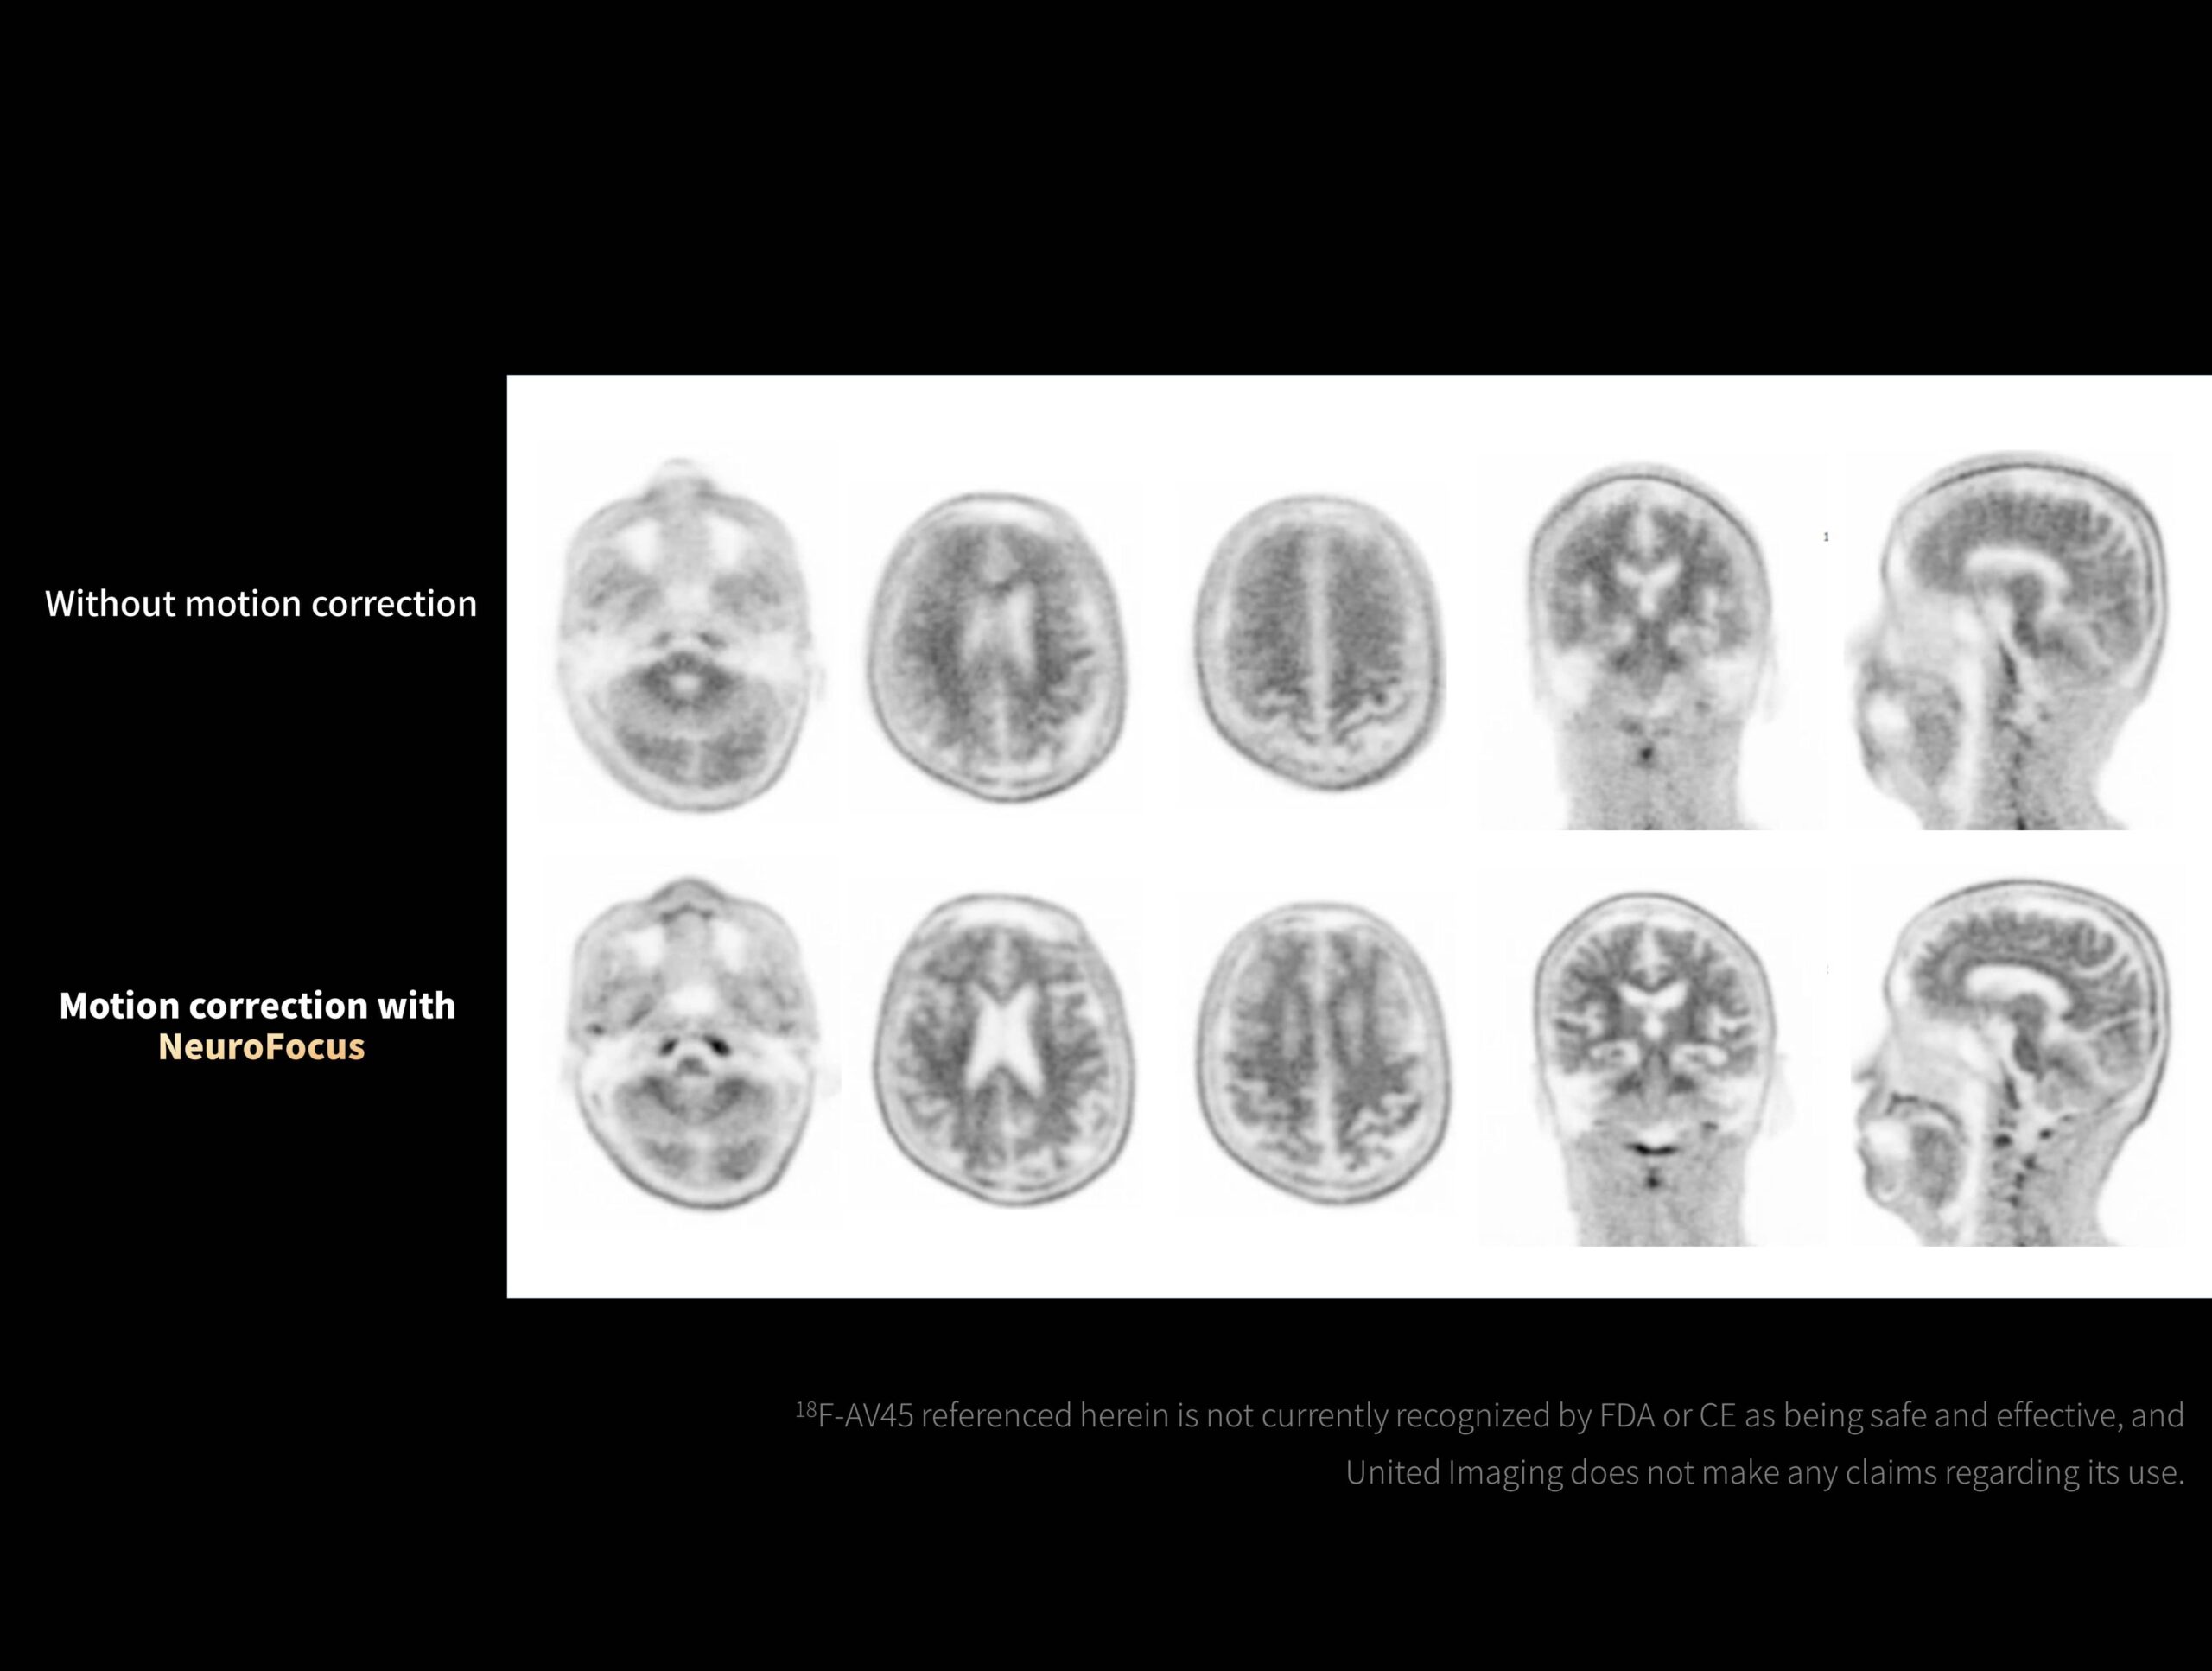

NeuroFocus reduce artefactele de mișcare în imagistica 18-F-AV45